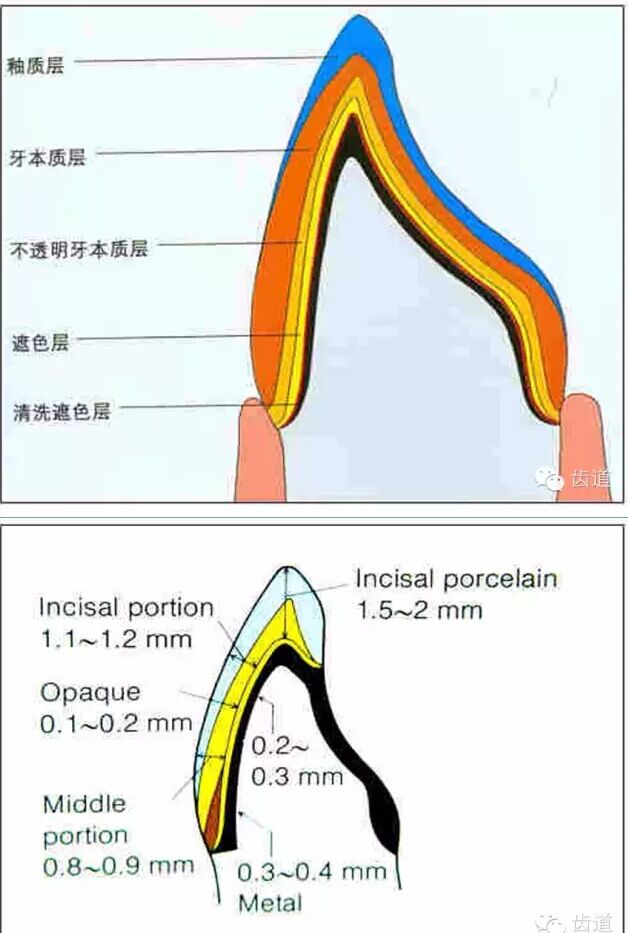

l預留修復體的空間

l防止過度預備(造成牙髓激惹)

l保留活髓(保留牙體的整體性和韌性)

l過度預備抗力形喪失